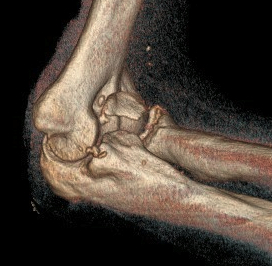

Regan and Morrey classification of transverse coronoid fractures

Elbow stability related to size of coronoid fragment

| Type I | Type II | Type II |

|---|---|---|

| Small coronoid process fracture | 50% of coronoid process | > 50% coronoid process |

| Usually stable |

Capsular attachment Elbow unstable |

Capsule + MCL attachment Elbow unstable

|